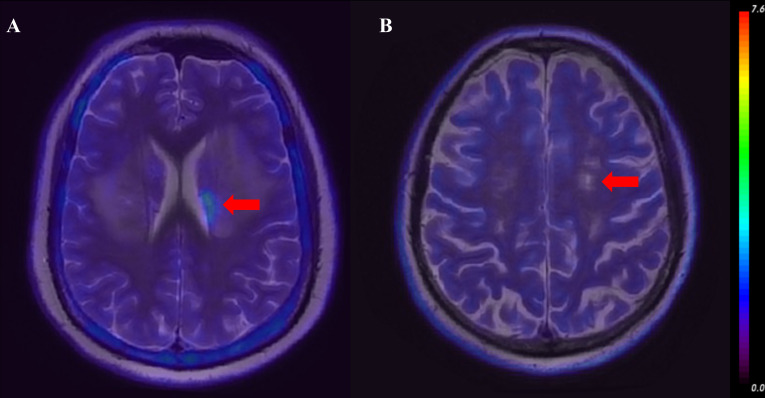

Methods: A retrospective analysis was conducted on 19 patients with NPSLE and 10 patients with non-NPSLE, who underwent [18F] DPA-714 PET/MRI. Diagnoses of SLE and NPSLE followed American College of Rheumatology (ACR) classification and Systemic Lupus International Collaborating Clinics (SLICC) Model B criteria. T2-weighted MRI lesions served as regions of interest (ROI), coregistered to PET for cross-modality quantitative analysis. The maximum uptake (SUVmax) and mean uptake (SUVmean) of brain lesions for each patient was measured. Group differences in SUVmax and SUVmean were compared. Clinical associations were conducted using Pearson correlation, and differentiation between non-NPSLE and NPSLE was performed by logistic regression analysis.

Results: SUVmax was significantly higher in the NPSLE group than in the non-NPSLE group (p<0.01), while there was no significant difference in SUVmean (p>0.05). SUVmax was correlated with clinical assessment scores (SLICC/ACR: r=0.43, p=0.02; modified Rankin Scale: r=0.41, p=0.04; SLE Disease Activity Index: r=0.41, p=0.03), and no significant correlation was found for SUVmean. In logistic regression analysis, only the model based on SUVmax alone was significant (p=0.01). In ROC analysis, the area under the curve (AUC) of SUVmax (0.83) was higher than that of SUVmean (0.68), and Model 4 (SUVmax+SUVmean + Interaction) showed the best diagnostic performance (AUC=0.94).

Conclusions: Patients with NPSLE and non-NPSLE showed distinct TSPO uptake in brain lesions, indicating different pathophysiology. TSPO PET/MR may serve as a potential imaging biomarker for differentiating NPSLE, providing insights for clinical diagnosis and mechanistic stratification in SLE.